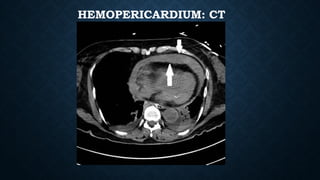

HEMOPERICARDIUM

• Hemopericardium refers to the presence of blood within the pericardial cavity. Can occur

from blunt/penetrating/deceleration trauma.

• Plain radiograph

• enlargement of the cardiac silhouette may be present but chest x-rays are insensitive and

non-specific.

• the "straight left heart border" is an infrequent sign with low sensitivity (~40%) for

hemopericardium in penetrating trauma patients.

• ​

the Oreo cookie sign on lateral CXR.

HEMOPERICARDIUM: CT